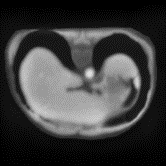

In clinical practice, well-aligned multi-modal images, such as Magnetic Resonance (MR) and Computed Tomography (CT), together can provide complementary information for image-guided therapies. Multi-modal image registration is essential for the accurate alignment of these multi-modal images. However, it remains a very challenging task due to complicated and unknown spatial correspondence between different modalities. In this paper, we propose a novel translation-based unsupervised deformable image registration approach to convert the multi-modal registration problem to a mono-modal one. Specifically, our approach incorporates a discriminator-free translation network to facilitate the training of the registration network and a patchwise contrastive loss to encourage the translation network to preserve object shapes. Furthermore, we propose to replace an adversarial loss, that is widely used in previous multi-modal image registration methods, with a pixel loss in order to integrate the output of translation into the target modality. This leads to an unsupervised method requiring no ground-truth deformation or pairs of aligned images for training. We evaluate four variants of our approach on the public Learn2Reg 2021 datasets \cite{hering2021learn2reg}. The experimental results demonstrate that the proposed architecture achieves state-of-the-art performance. Our code is available at https://github.com/heyblackC/DFMIR.